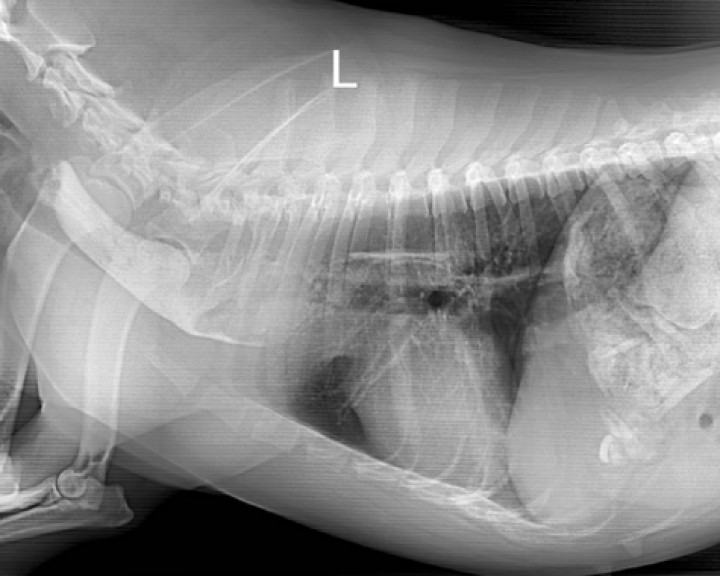

Acude a consulta una hembra de raza American Staffordshire de 2 años y 22,8 kg. Los propietarios comentan que unas horas antes se había comido parte de un hueso de jamón y, desde entonces, tenía mucha salivación y estaba decaída. En la exploración física su temperatura era de 39,4 ºC, sus mucosas estaban rosadas y el tiempo de relleno capilar era menor de 2 segundos, presentando abundante sialorrea. La auscultación cardiopulmonar era normal. No presentaba dolor a la palpación abdominal. En la analítica sanguínea se observaba monocitosis (1,79 K/μL; rango normal 0,16-1,12 K/μL) e incremento de la fosfatasa alcalina (122 U/L; rango 13-83 U/L). Se realizaron radiografías de la cavidad torácica (Fig. 1).

<p>(<strong>A</strong>) Radiografía de la cavidad torácica en proyección lateral derecha. (<strong>B</strong>) Radiografía de la cavidad torácica en proyección ventrodorsal.</p>

Figura 1

(A) Radiografía de la cavidad torácica en proyección lateral derecha. (B) Radiografía de la cavidad torácica en proyección ventrodorsal.